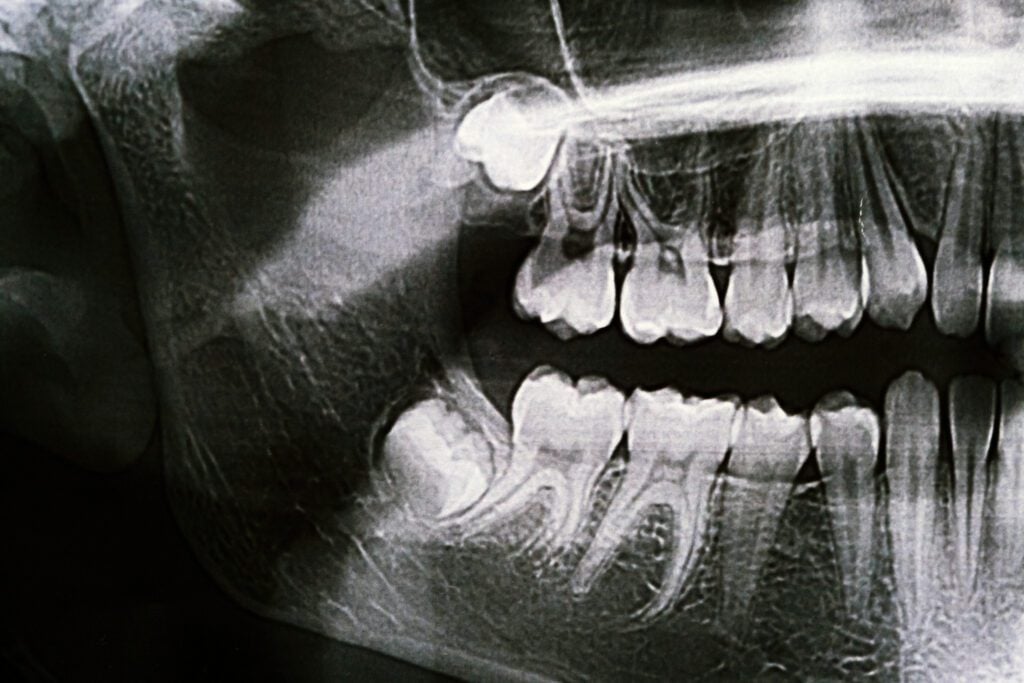

The average adult mouth is designed to hold around 28 teeth comfortably, but most adults end up with 32. The additional four teeth are called wisdom teeth or third molars. When there isn’t enough room for them, the wisdom teeth become blocked or impacted by the other teeth around them. This can become extremely traumatizing. If the wisdom tooth partially erupts, food can get trapped in the tissue surrounding it, which can lead to bacterial growth and possibly serious infection.

By removing wisdom teeth when a patient is a young adult, Drs. John Savon and Sara Engleman are able to prevent potential healing problems. When a person reaches the age of their mid-thirties, there are much higher risks involved in wisdom teeth removal. The best time to remove wisdom teeth is generally between the ages of fifteen to eighteen.